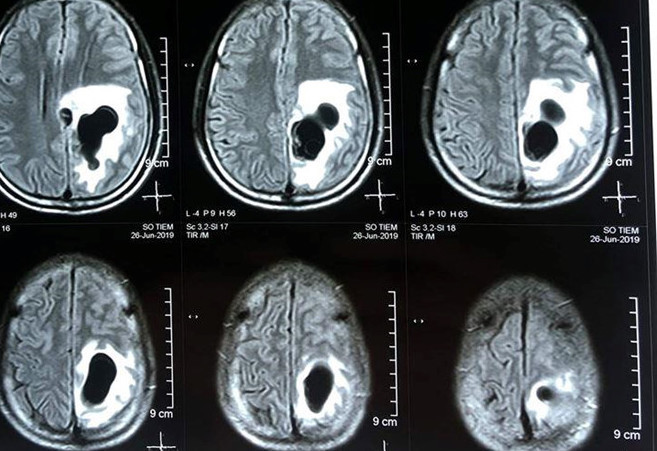

TPO - Kết quả chụp CT não của người đàn ông 38 tuổi tại Nghệ An cho thấy có 5 ổ sán nằm rải rác trong não, trong đó có một ổ sán lớn trên đỉnh của bệnh nhân gây phù não.

Bệnh nhân là anh Lô Văn S. (38 tuổi, ngụ tại Qùy Hợp) bị đau đầu triền miên, liệt nửa người, khi nhập viện đã được bác sĩ Bệnh viện Hữu nghị Đa khoa Nghệ An phát hiện có sán trong não. Theo lời kể của bệnh nhân trước khi nhập viện, một tháng, bệnh nhân S. xuất hiện những cơn đau đầu từ nhẹ đến nặng rồi đau liên tục, uống thuốc giảm đau không hiệu quả. Cách đây 1 tuần, bệnh nhân đau đầu nhiều, buồn nôn, sốt, tê yếu nửa người, tri giác chậm, nên được người nhà đưa vào viện cấp cứu. Kết quả chụp CT não cho thấy có 5 ổ sán nằm rải rác trong não, trong đó có một ổ sán lớn trên đỉnh của bệnh nhân gây phù não. Bệnh nhân được chỉ định can thiệp ngoại khoa để lấy được trọn vẹn ổ nang sán khỏi não.